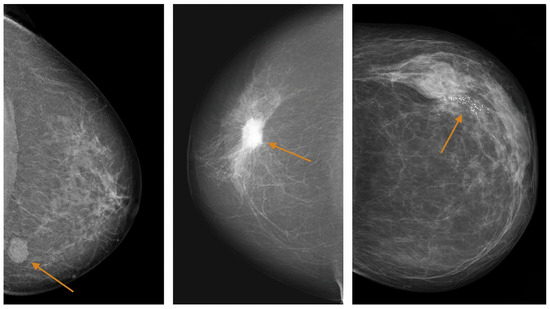

Advances in Medical Image Processing for Early Breast Cancer Detection: Classical Techniques and Deep Learning Perspectives

Breast cancer is the most common malignancy among women and a leading cause of cancer-related mortality, making early and accurate detection essential. This review summarises advances in breast imaging and computational diagnostics across mammography, ultrasound, and magnetic resonance imaging (MRI), highlighting challenges in differentiating benign from malignant lesions and identifying rarer tumour types. Key preprocessing steps—denoising, deblurring, and contrast enhancement—are reviewed as they improve image quality prior to analysis. Classical methods (e.g., thresholding, edge detection, and region growing) are compared with deep learning approaches for segmentation and classification. CNNs, RNNs, and emerging transformer-based models consistently outperform handcrafted pipelines, with representative studies reporting 5–15% gains in AUC/accuracy and deep models achieving AUC > 0.85–0.95 on several benchmarks. The review also discusses dataset constraints, common evaluation metrics (AUC, Dice, sensitivity, specificity), and clinical translation barriers such as interpretability and domain shift. Overall, AI-driven methods show strong potential to enhance early detection and support improved breast cancer outcomes. Full article

Show Figures

Figure 1